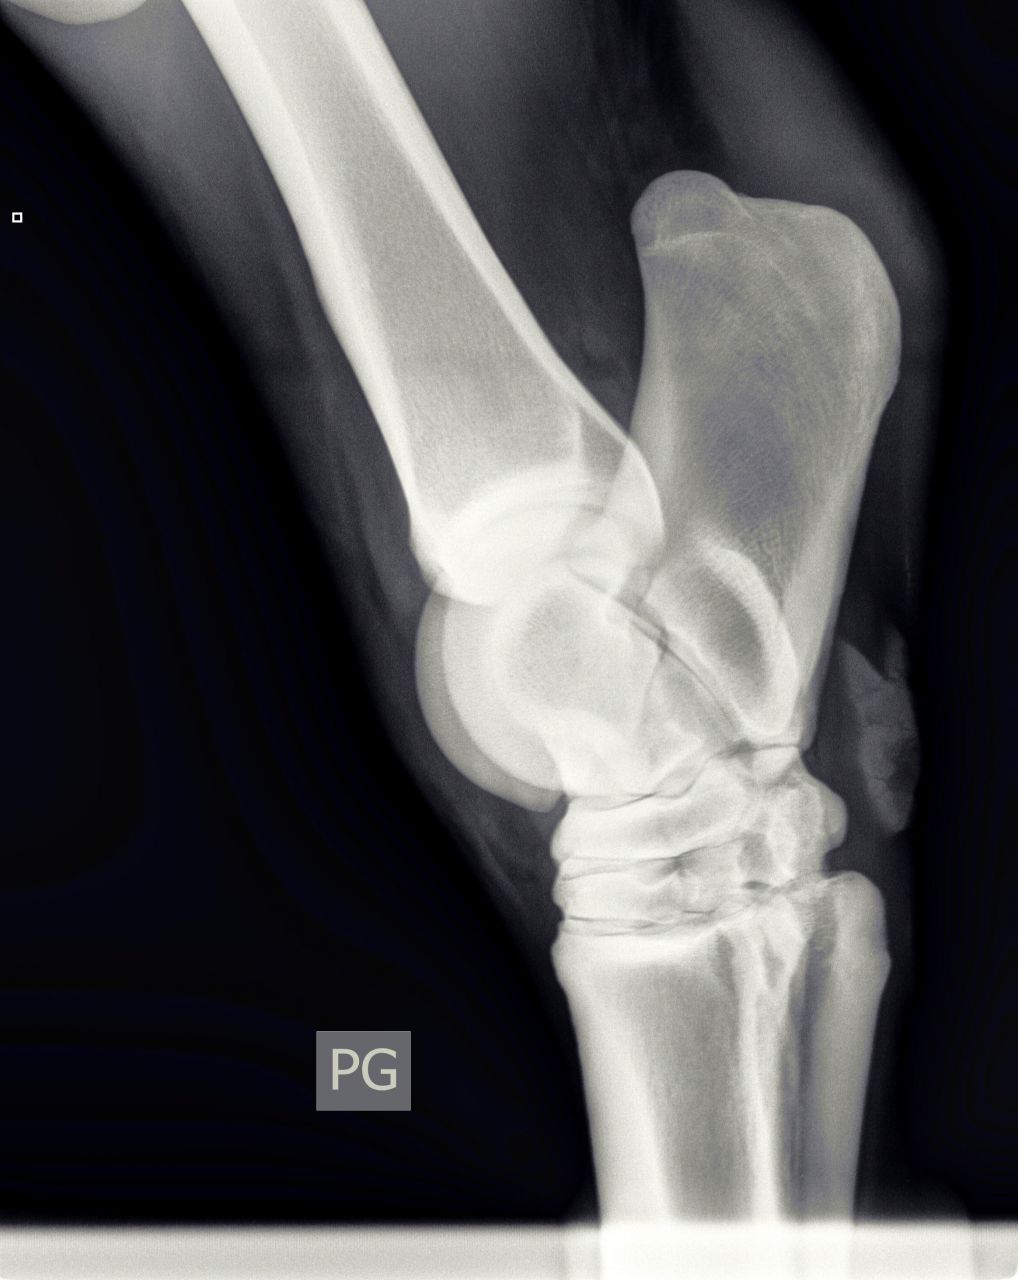

| Dire merci | Bonjour, le vétérinaire vient de diagnostiquer un début d'éparvin sur un des postérieurs de ma jument. Voici les radios : [url=https://www.1cheval.com/membre/services/photos/images/198166.jpg" class='zoombox zgallery3311504' ] ![]() [/url] [url=https://www.1cheval.com/membre/services/photos/images/198165.jpg" class='zoombox zgallery3311504' ] ![]() [/url] [url=https://www.1cheval.com/membre/services/photos/images/198164.jpg" class='zoombox zgallery3311504' ] ![]() [/url] il me propose comme soins : tildren en IV et ferrure avec plus d'éponge Que pensez-vous de ce traitement? je suis perdu quant à la marche à suivre (le traitement vaut 500€ et sans garanti de résultat même si le véto a bon espoir) Ceci dit, je viens de rencontré quelqu'un à qui ce même véto à déconseillé le tildren pour sa jument qui a un éparvin. Une amie en a parlé à son véto (spé équin aussi) qui lui a dit qu'on pouvait tenter aussi les ondes de choc. Je ne connais pas le prix Quelqu'un a-t-il déjà testé sur l'éparvin? Que faire d'autre? J'ai bien fait cure d'harpagophyt, sans amélioration. en voici plus sur ma jument : Celle-ci est une arabo-appalossa de 12 ans, née chez moi, débourrée à 5-6 ans et qui fait du loisir modéré. Elle s'est mise à boiter suite à une endurance (10 km) où il y avait un fort dénivelé en tout début et toute fin de (au point que je suis descendu d'elle pour descendre le chemin en crabe). La jument était largement entrainée avant (elle aurait pu courir une 20 voir une 40) elle est au repos depuis (ca fait 3 mois et demi) et j'ai l'impression que la boiterie s'aggrave un peu (c'est intermittent) lorsque je l'ai emmener au vétérinaire, elle ne boitait pas, les tests de flexions ont ré-déclenché la boiterie. La jument est ferrée en rolls des 4 pieds depuis 6 mois (et plus d'un an des antérieurs) |